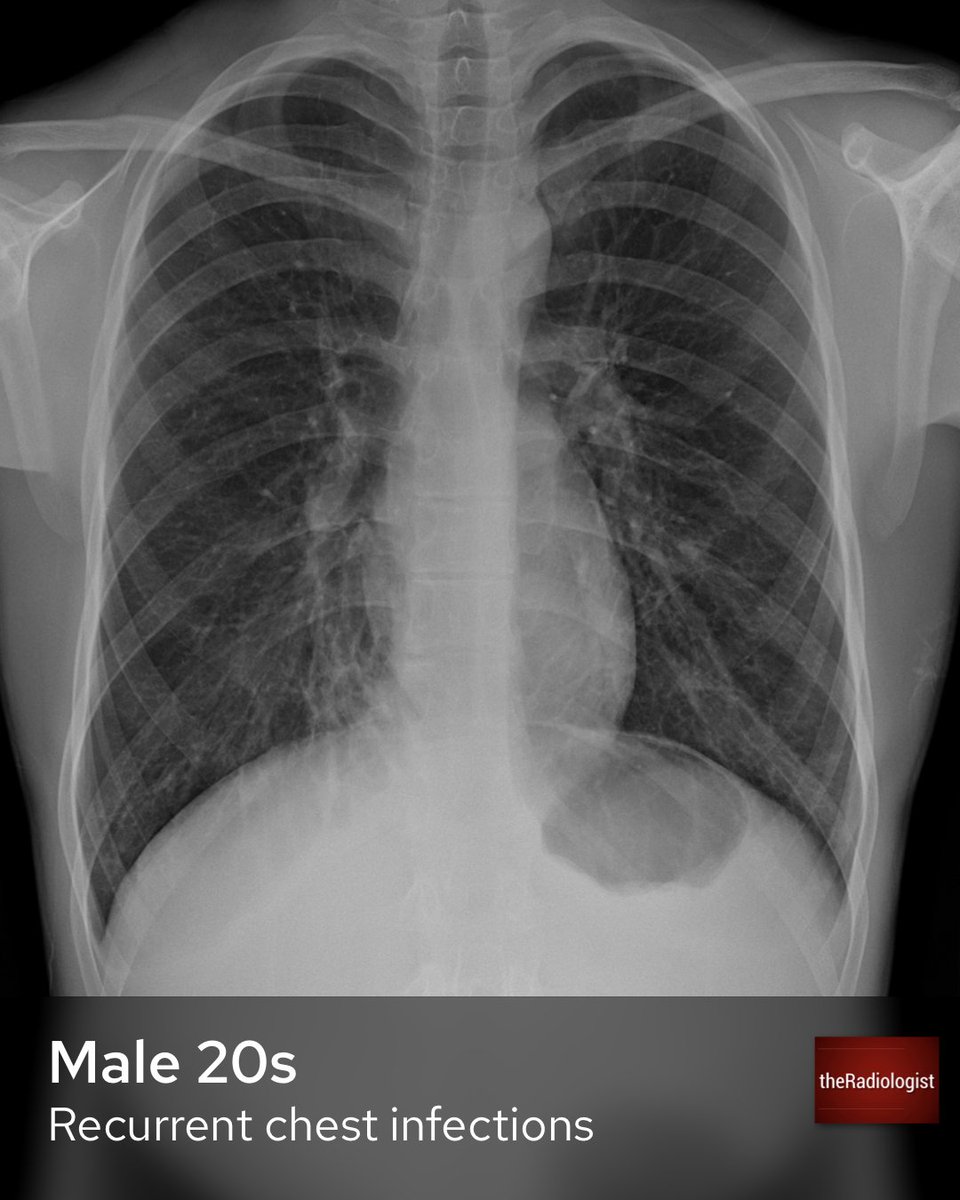

From twitter.com

theRadiologist on Twitter "A male in his 20s presents with recurrent Do All Chest Infections Show Up On Xray The interpretation of a chest film. These white spots indicate that the alveoli are filled with pus. Blood tests and phlegm (sputum). In fact every radiologst should be an expert in chest film reading. Imaging plays an integral role in the diagnosis and management of suspected pulmonary infections and may reveal useful signs on chest radiographs and ct scans. Chest. Do All Chest Infections Show Up On Xray.